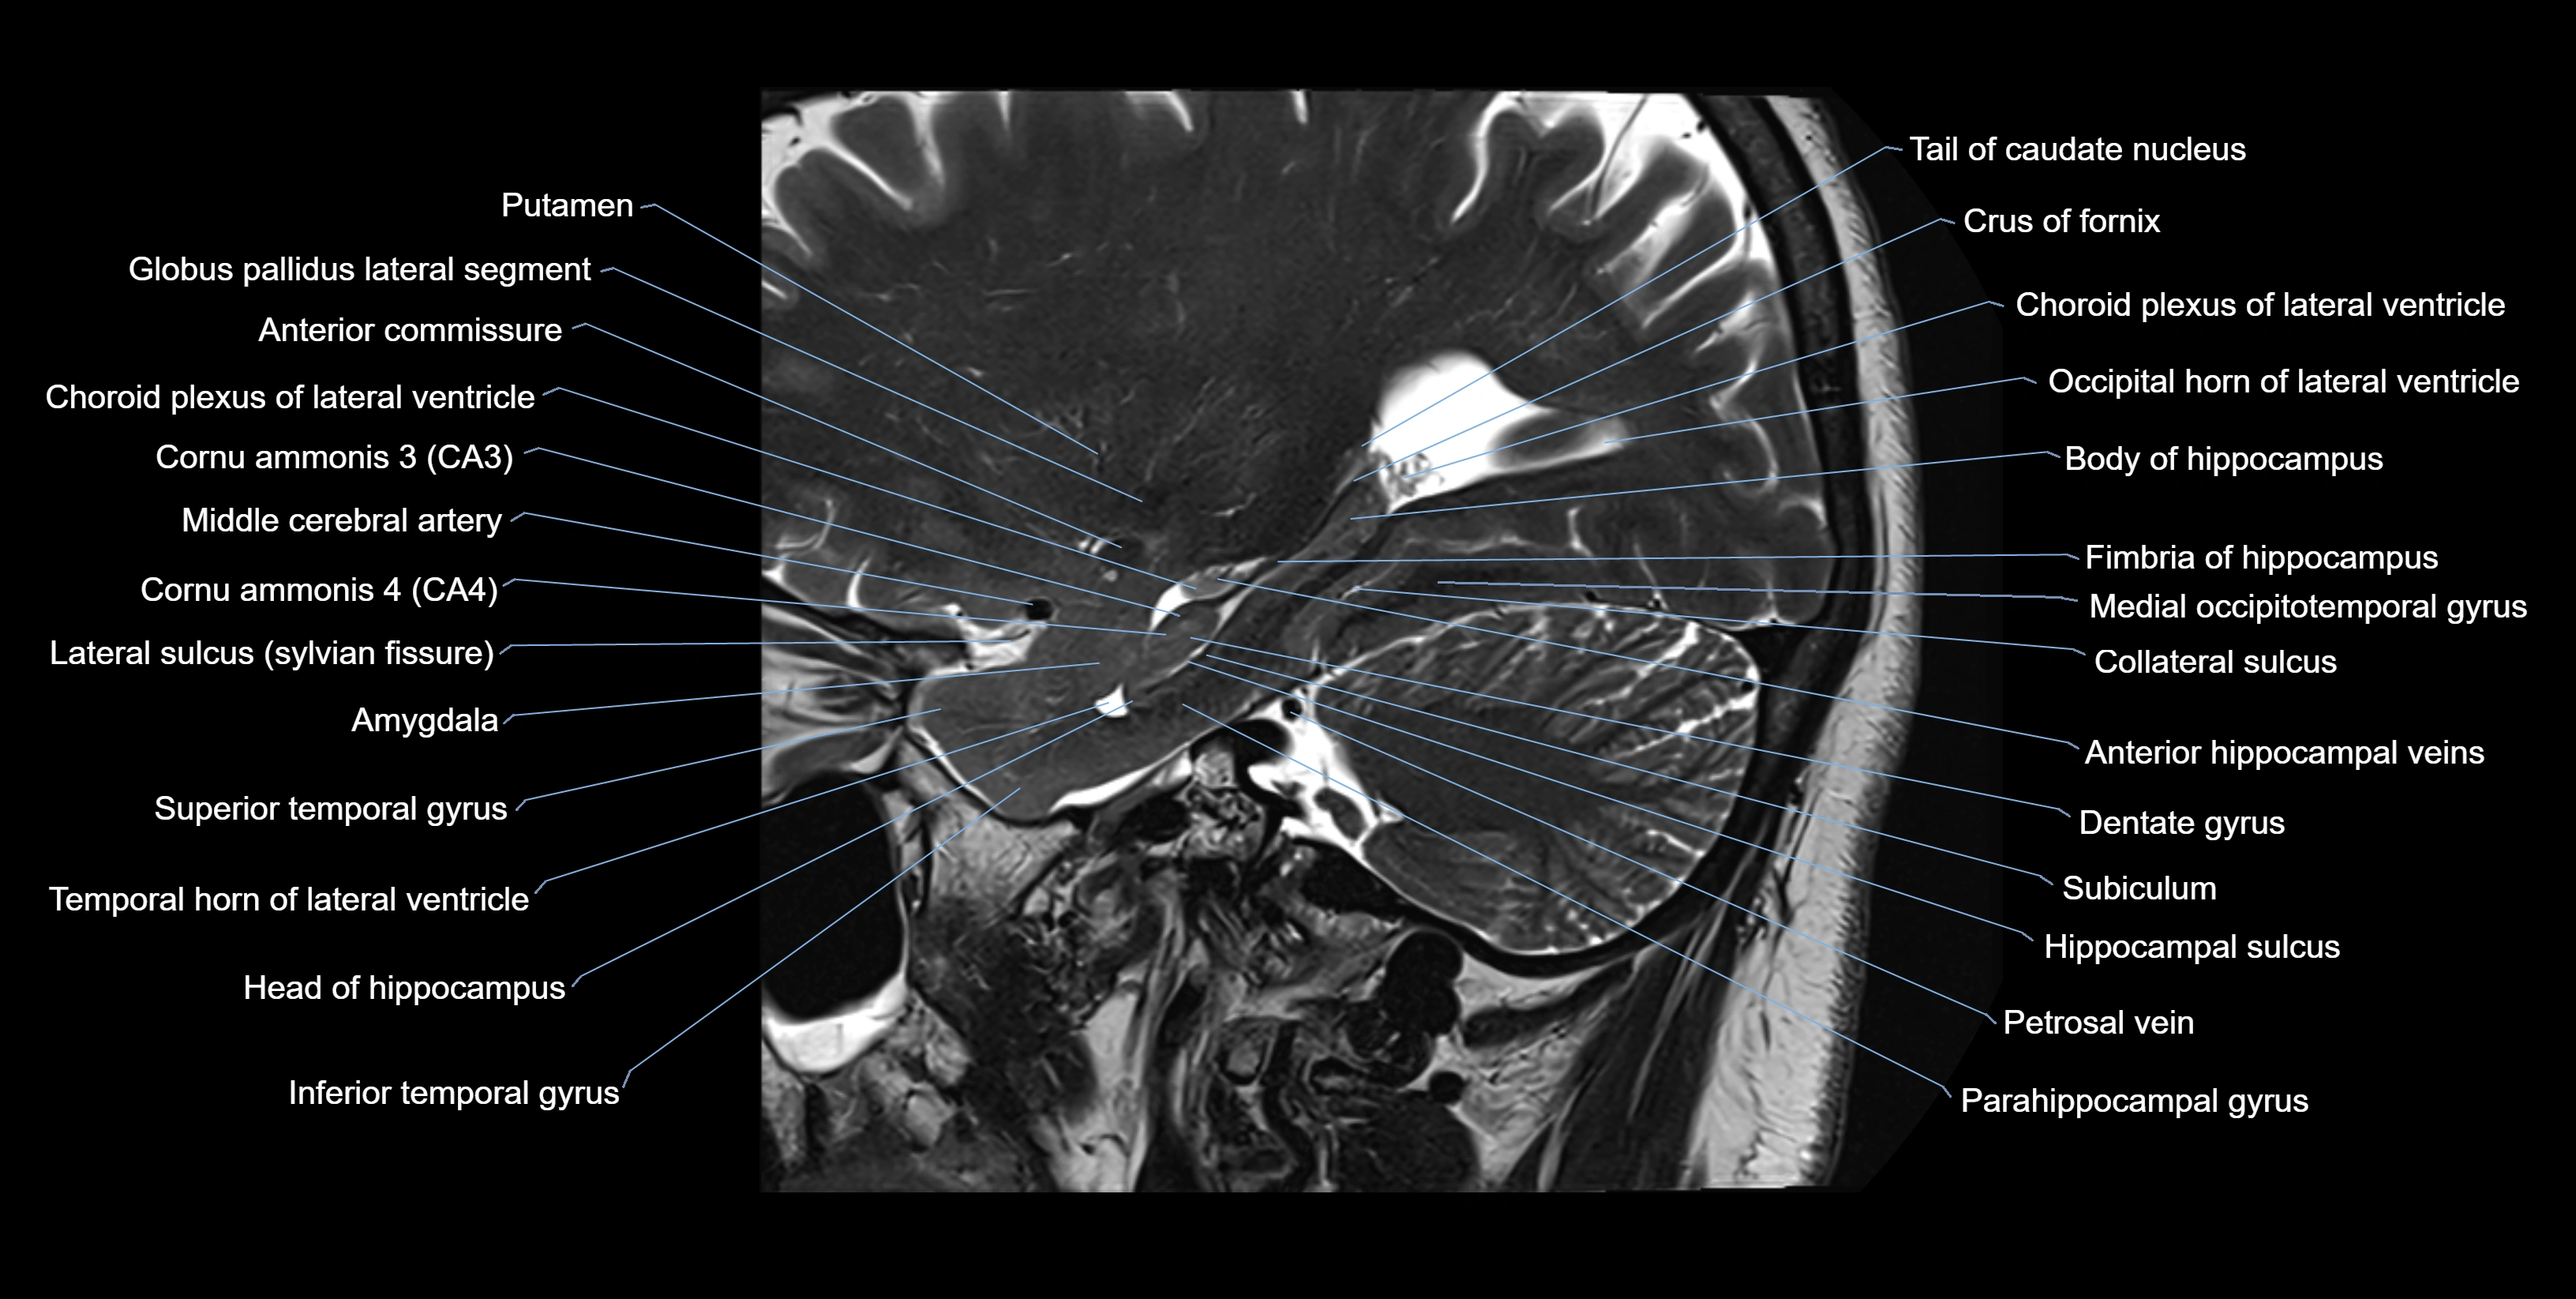

MRI images

image